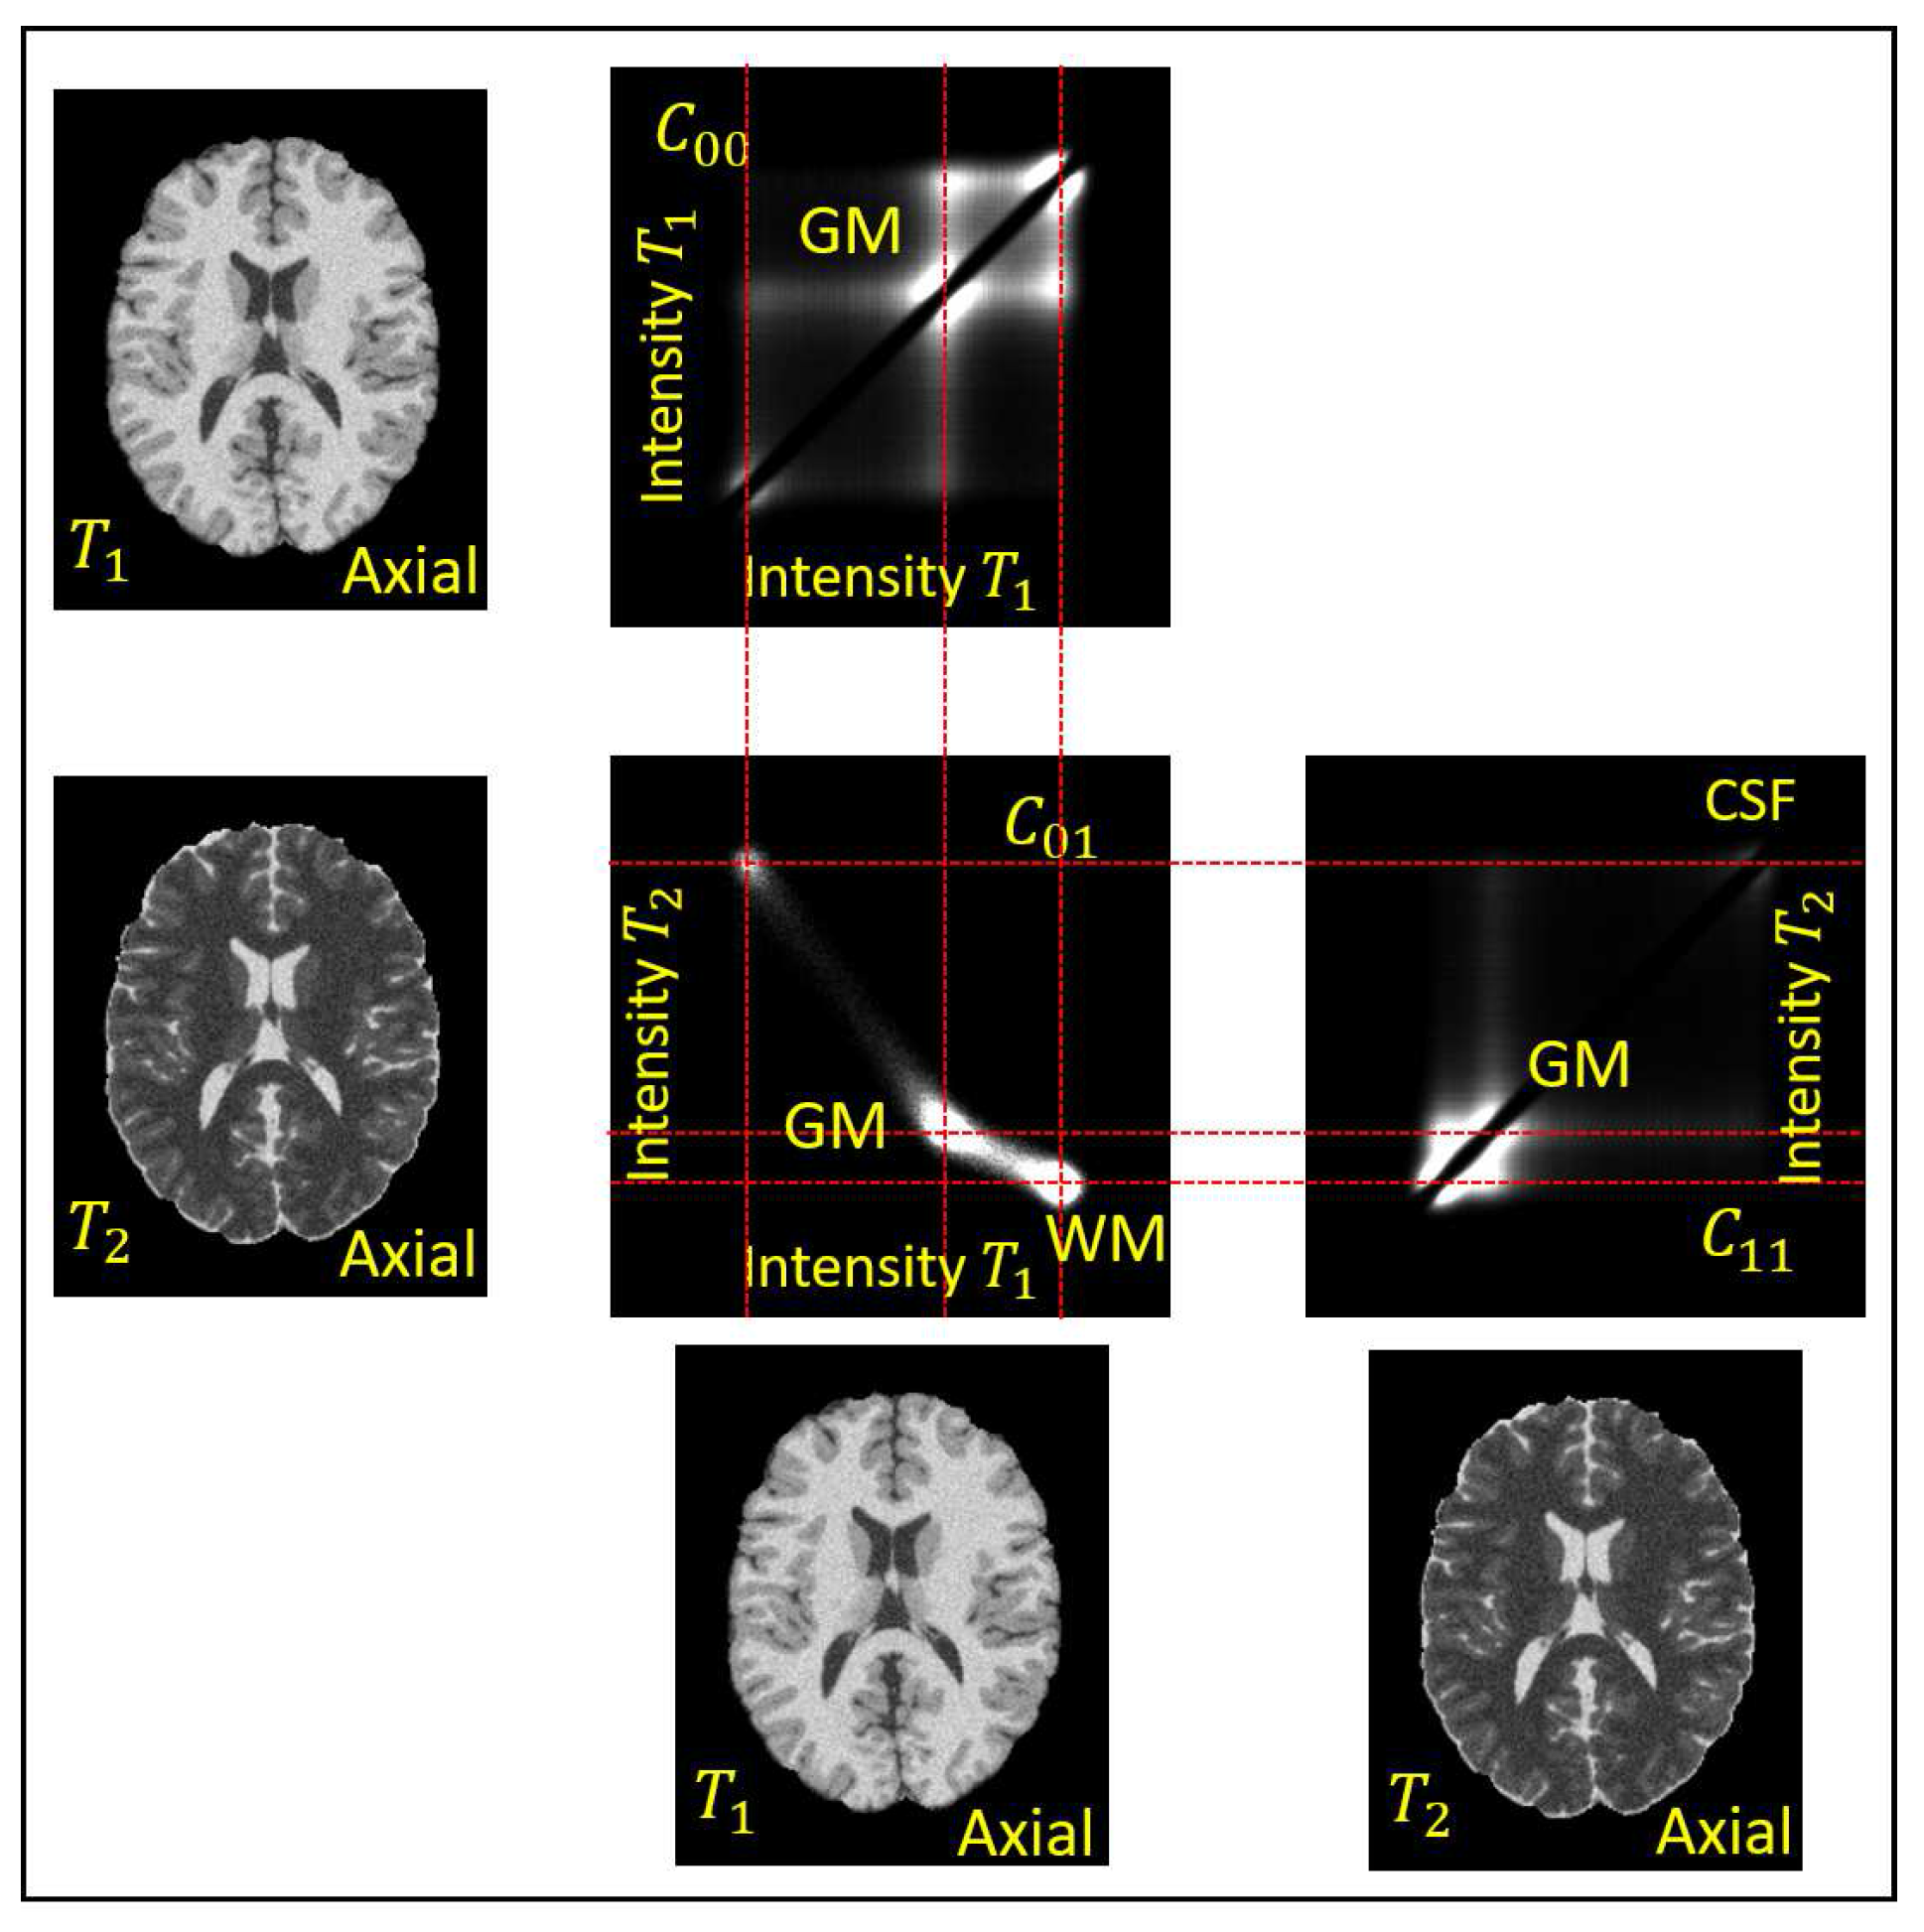

They give the auto-co-occurrences for and the joint-co-occurrences for . The auto-co-occurrences are dominated by their diagonal entries and thus they are weighted down with the sigmoid . The different tissues, or tissues interfaces, of the anatomic images are assumed to correspond to distinct modes of the co-occurrence statistics. An example of the co-occurrences of a pair of and BrainWeb phantom images [37] is in Figure 4. A median filtering is applied to to remove the high frequency noise . The objective of the analysis is to separate the remaining two products in , present in Equation (9) to obtain the factors and , respectively.

Figure 4.

The auto-co-occurrence statistics and the joint-co-occurrence statistics of a and a image of the BrainWeb phantom without non-uniformity, , and with noise of [37]. The densities in the statistics are displayed in logarithmic scale. The individual distributions of the Gray Mater (GM), White Matter (WM), and Cerebrospinal Fluid (CSF) are apparent.